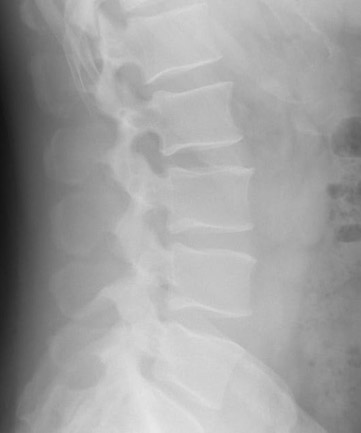

Chrbtica sa skladá z stavcov a medzi nimi sa nachádzajú medzistavcové platničky, ktoré pôsobia ako tlmiče nárazov a umožňujú flexibilitu pohybu. Každá platnička má vonkajší väzivový obal (anulus fibrosus) a vnútorné gélové jadro (nucleus pulposus).

Hernia disku nastáva, keď sa vnútorné jadro platničky vysunie cez poškodený obal a začne tlačiť na miechu alebo nervové korene. Tento tlak môže spôsobovať bolesť, brnenie či slabosť v končatinách.

- Magnetická rezonancia (MRI) – najpresnejšia metóda na zobrazenie medzistavcových platničiek a nervových štruktúr.

- Počítačová tomografia (CT) – využíva sa v prípadoch, keď MRI nie je dostupná.

- Röntgen – síce nezobrazí samotnú herniu, ale pomôže vylúčiť iné problémy s chrbticou.